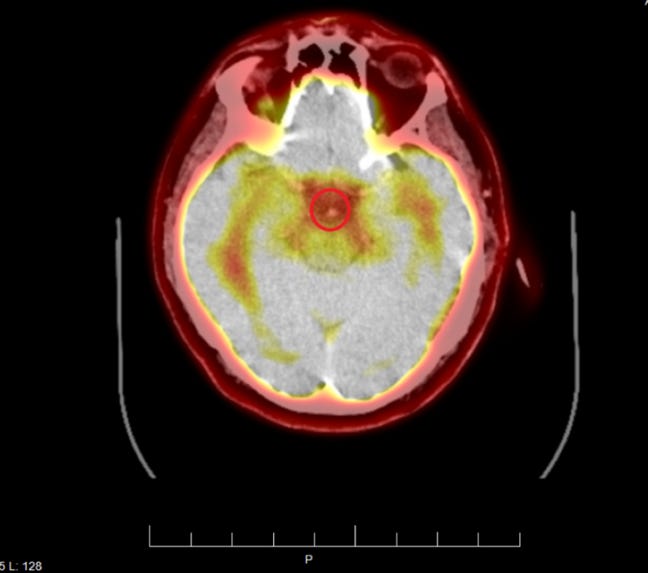

L'examen TEP cérébral haute définition montre la micropuce au même endroit :